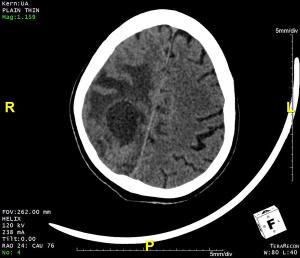

75-year-old male presented with left-sided weakness, headache, and altered sensorium.